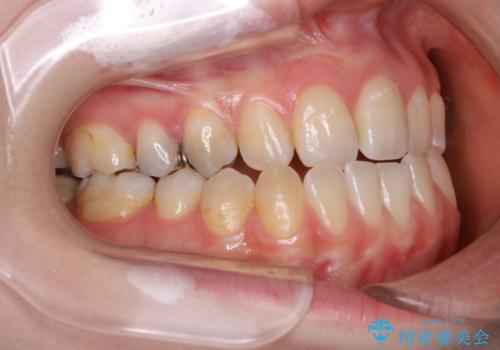

- 受け口で、前歯の嚙み合わせが気になるとの事でご相談にいらした方です。先天的に右上犬歯がなく、左上犬歯も小さい状態でした。矯正治療にて周囲の歯を動かして歯のスペースを確保した上で、被せものにて歯を作っていきました。

歯科技工士さんの熟練した技術により、周囲の歯としっかりなじむ天然歯のような被せ物をお作りすることが出来ました。

矯正治療と補綴治療をうまく組み合わせることで、美しい口元に仕上げることが出来ました。矯正治療、補綴治療をまとめて行える総合歯科治療を体現した治療といえます。